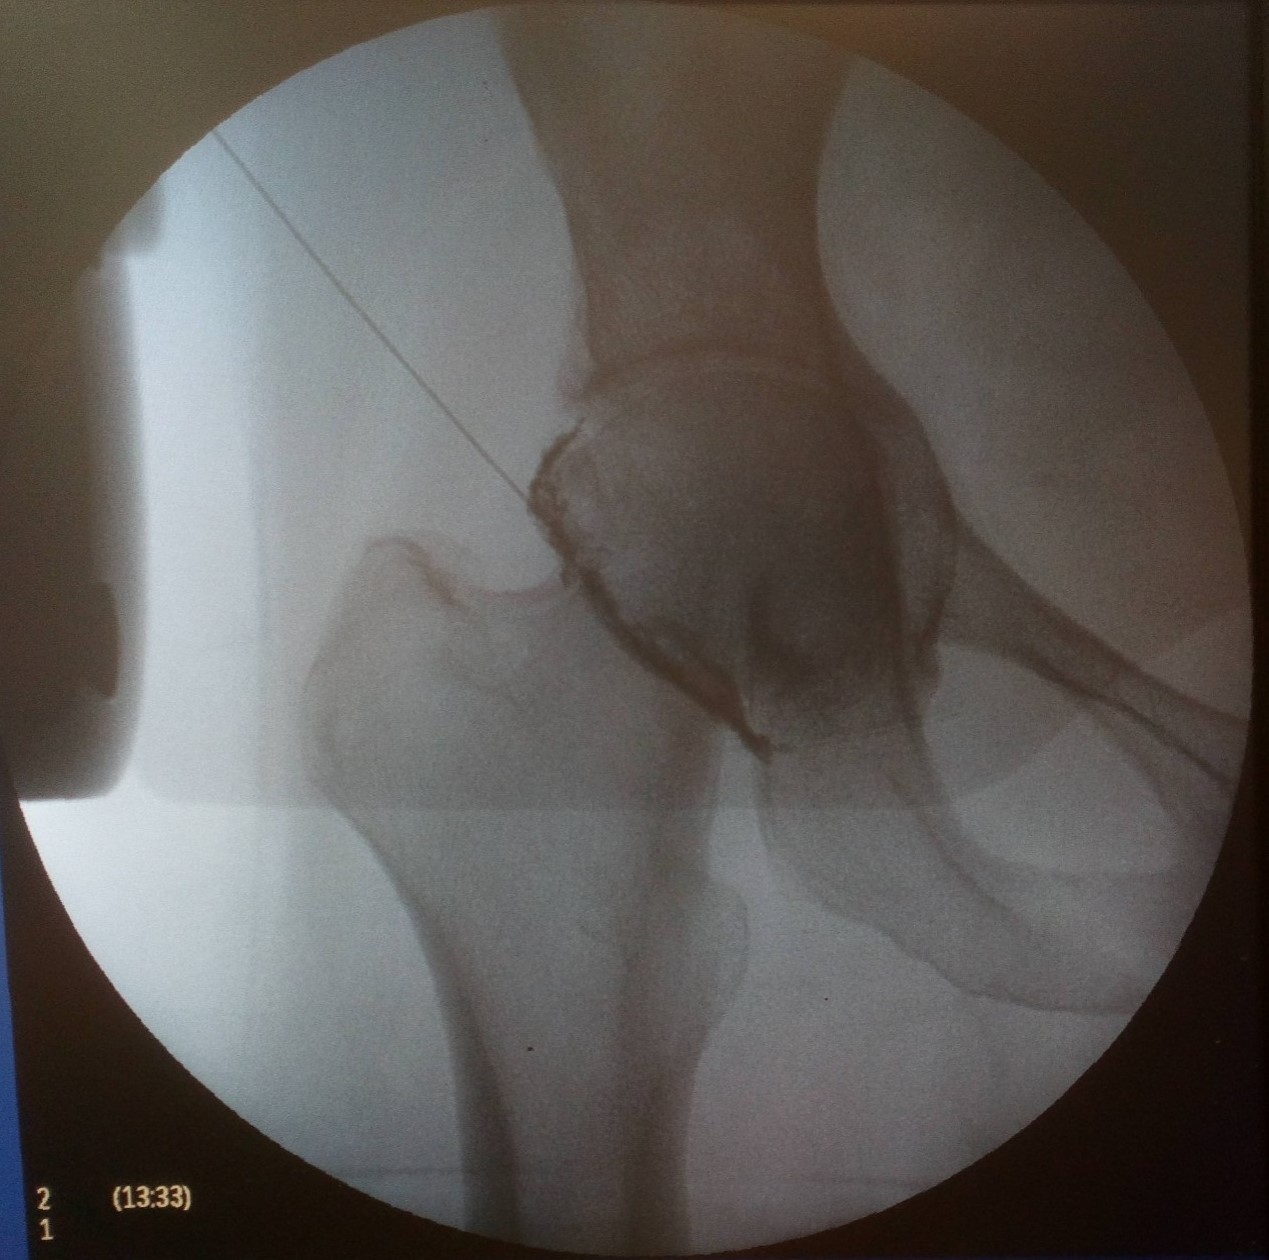

Ασθενής με άλγος δεξιού ισχίου

Ασθενής 53 ετών, γυμνάστρια, με αιφνίδιο άλγος δεξιού ισχίου από 2ετίας. Υπεβλήθη σε διάφορες θεραπείες σε άλλα κέντρα χωρίς αποτέλεσμα. Η ακτινογραφία έδειξε ότι υπάρχει οστεοαρθρίτιδα με αρθροκατατάδυση. Λόγω του νεαρού της ηλικίας απεφασίσθη να μην υποβληθεί σε ολική αρθροπλαστική. Πραγματoποιήθηκε έγχυση ισχίου με υαλουρονικό και τοπικό αναισθητικό. Η ασθενής ένιωσε άμεσα ανακούφιση που διατηρείται έως σήμερα 2 χόνια μετά